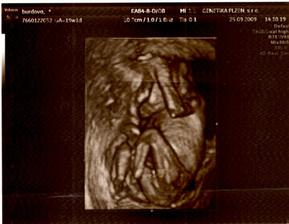

berija

13. bře 2009

Nelinka -tak jde čas🙂